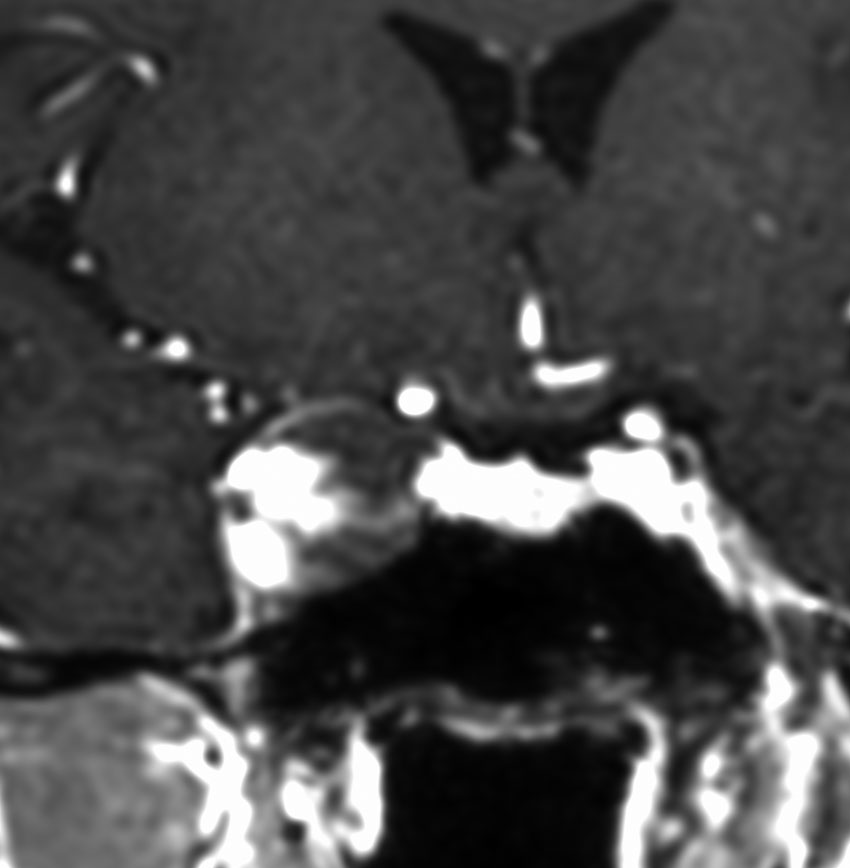

静脈性血管腫(静脈奇形)の合併を見つける方法

左は脳出血のCTです。海綿状血管腫からの出血を疑ったので造影のMRI(右の写真)をしました。血腫の周りに細い線がたくさん見えます。これが静脈奇形(静脈性血管腫)です。脳血管撮影DSAをしなくてもこの合併はわかるのです。この静脈奇形を手術で傷つけるとかなり広い範囲で脳梗塞がおきる可能性があります。